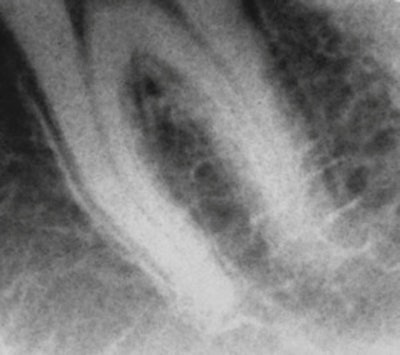

Real Time Imaging Technologies has developed a prototype that provides low-dose dental imaging and dental fluoroscopy imaging at comparable resolution to existing dental technologies. Images courtesy of Real Time Imaging Technologies."Despite its early introduction to dentistry in 1896, the use of fluoroscopy in this profession has been inconsistent over the last 55 years due to radiation dosage concerns and the large size and low resolution of the devices used," he and his colleagues wrote in 2010 (Chinese Journal of Dental Research, Spring 2010, Vol. 13:1, pp. 23-29).

Raw image obtained from a dental fluoroscopic imaging system intraoral/extraoral sensor working prototype on a dental phantom at 0.2 mA/0.033-second exposure time.